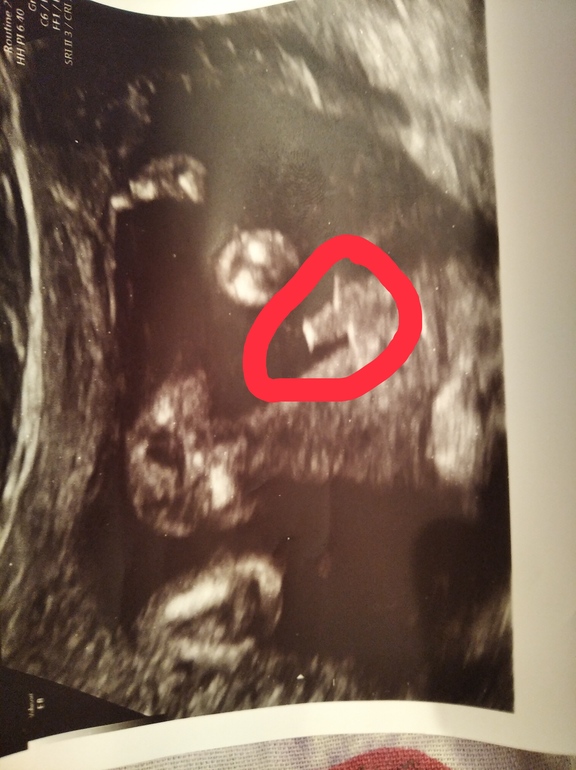

Всё началось где-то в 2 месяца. Педиатр сказала что у нас привычный поворот головы, посоветовала чаще держать на другом боку. Улучшений видно особо не было. Когда мы были на приёме в 4 месяца, нас направили к неврологу. Поставили под вопросом диагноз кривошея. Сегодня делали рентген, написали : "Отмечается клиновидная деформация тела с VI . Интранатальный компресионный перелом."